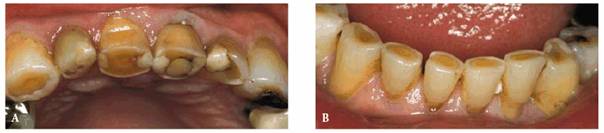

procedure can be seen in Figures 17-8A

and B 17-8C 17-8D 17-8E 17-8F 17-8G 17-8H and I, which show a 45-year-old man with

evidence of gingival and incisal abrasion, erosion, and abfraction. It is

Figure 17-8A and B: This 45-year-old man shows extreme tooth loss due to combination lesions both gingivally and incisally of abrasion, erosion, and abfraction.